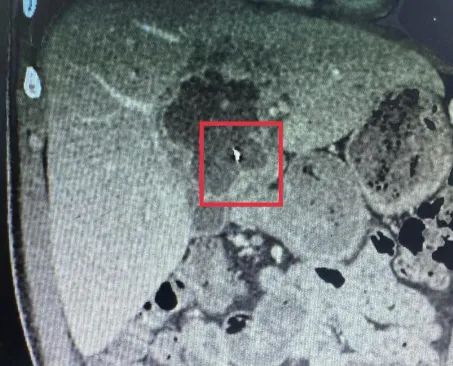

Qua thăm khám lâm sàng kết hợp siêu âm ổ bụng và chụp CT-scan, cho thấy ổ áp xe gan kích thước khoảng 5 x 6cm, bên trong có dị vật kim loại dài khoảng 6cm.